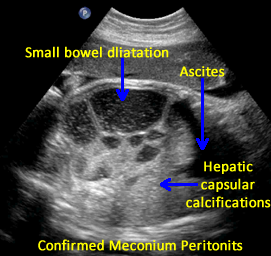

Above. Meconium peritonitis. Case 1. 36 6/7 weeks gestation. Transverse small bowel. Note small bowel dilatation and polyhydramnios.

Above. Meconium peritonitis. Case 1. 36 6/7 weeks gestation. Longitudinal small bowel. Note small bowel dilatation and mesenteric calcifications.

Above. Meconium peritonitis. Case 1. 36 6/7 weeks gestation. Again, note small bowel dilatation and mesenteric calcifications.

Above. Meconium peritonitis. Case 1. 36 6/7 weeks gestation. Note hepatic capsular calcifications and the presence of fetal ascites.